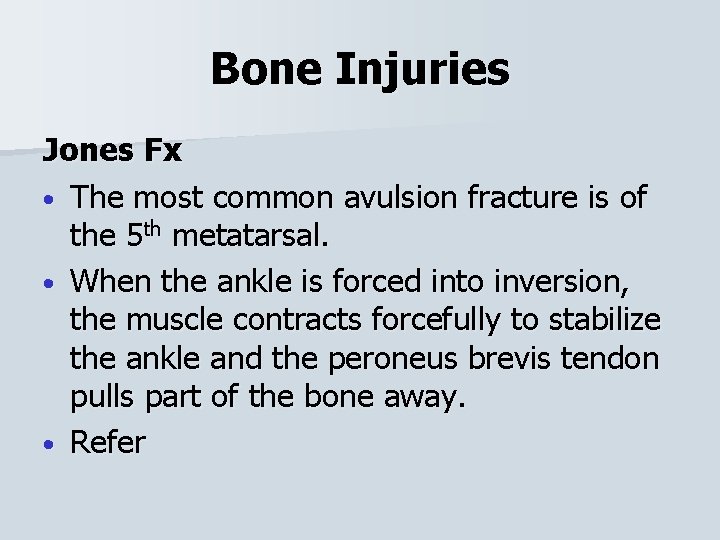

Bone Injuries Jones Fx • The most common avulsion fracture is of the 5 th metatarsal. • When the ankle is forced into inversion, the muscle contracts forcefully to stabilize the ankle and the peroneus brevis tendon pulls part of the bone away. • Refer

Bone Injuries Epiphyseal Fx • Distal tibia and fibula fracture of the epiphysis, or growth plates can become injured when the ankle is forced into plantar flexion and eversion. • The athlete will experience pain & swelling over the epiphysis and difficulty walking/running. • Splint the injury and refer to physician.